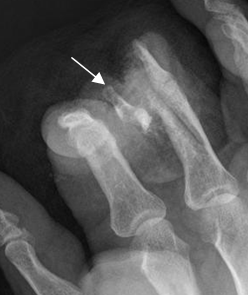

Fig 59 B. Luxofractura de Bennet.

A: Rx AP y B: Rx oblicua. Subluxación de la articulación carpometacarpiana del pulgar y fractura en la base del metacarpiano, por luxofractura de Bennet.

Fig 59 C. Luxofractura de Bennet.

A: Rx oblicua. Luxofractura de Bennet, con pequeño fragmento suelto medial.